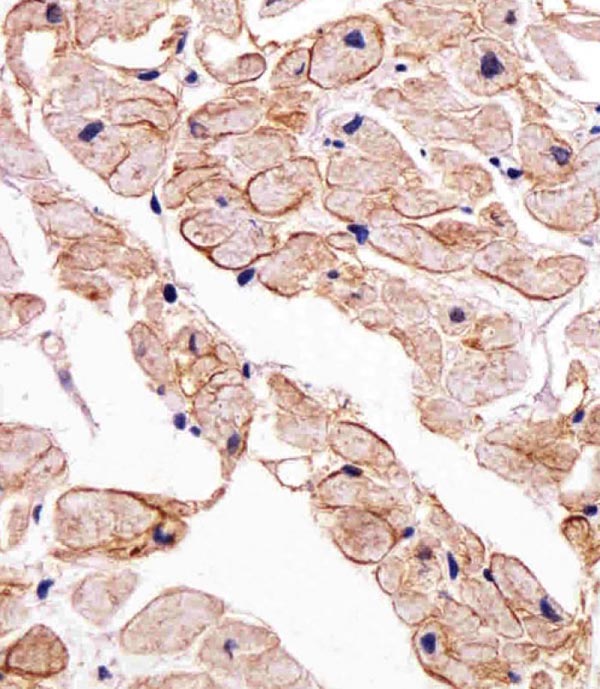

IHC (Immunohistochemistry)

(Immunohistochemical analysis of paraffin-embedded H. heart section using SGCG Antibody (Center). AAA286720 was diluted at 1:25 dilution. A undiluted biotinylated goat polyvalent antibody was used as the secondary, followed by DAB staining.)